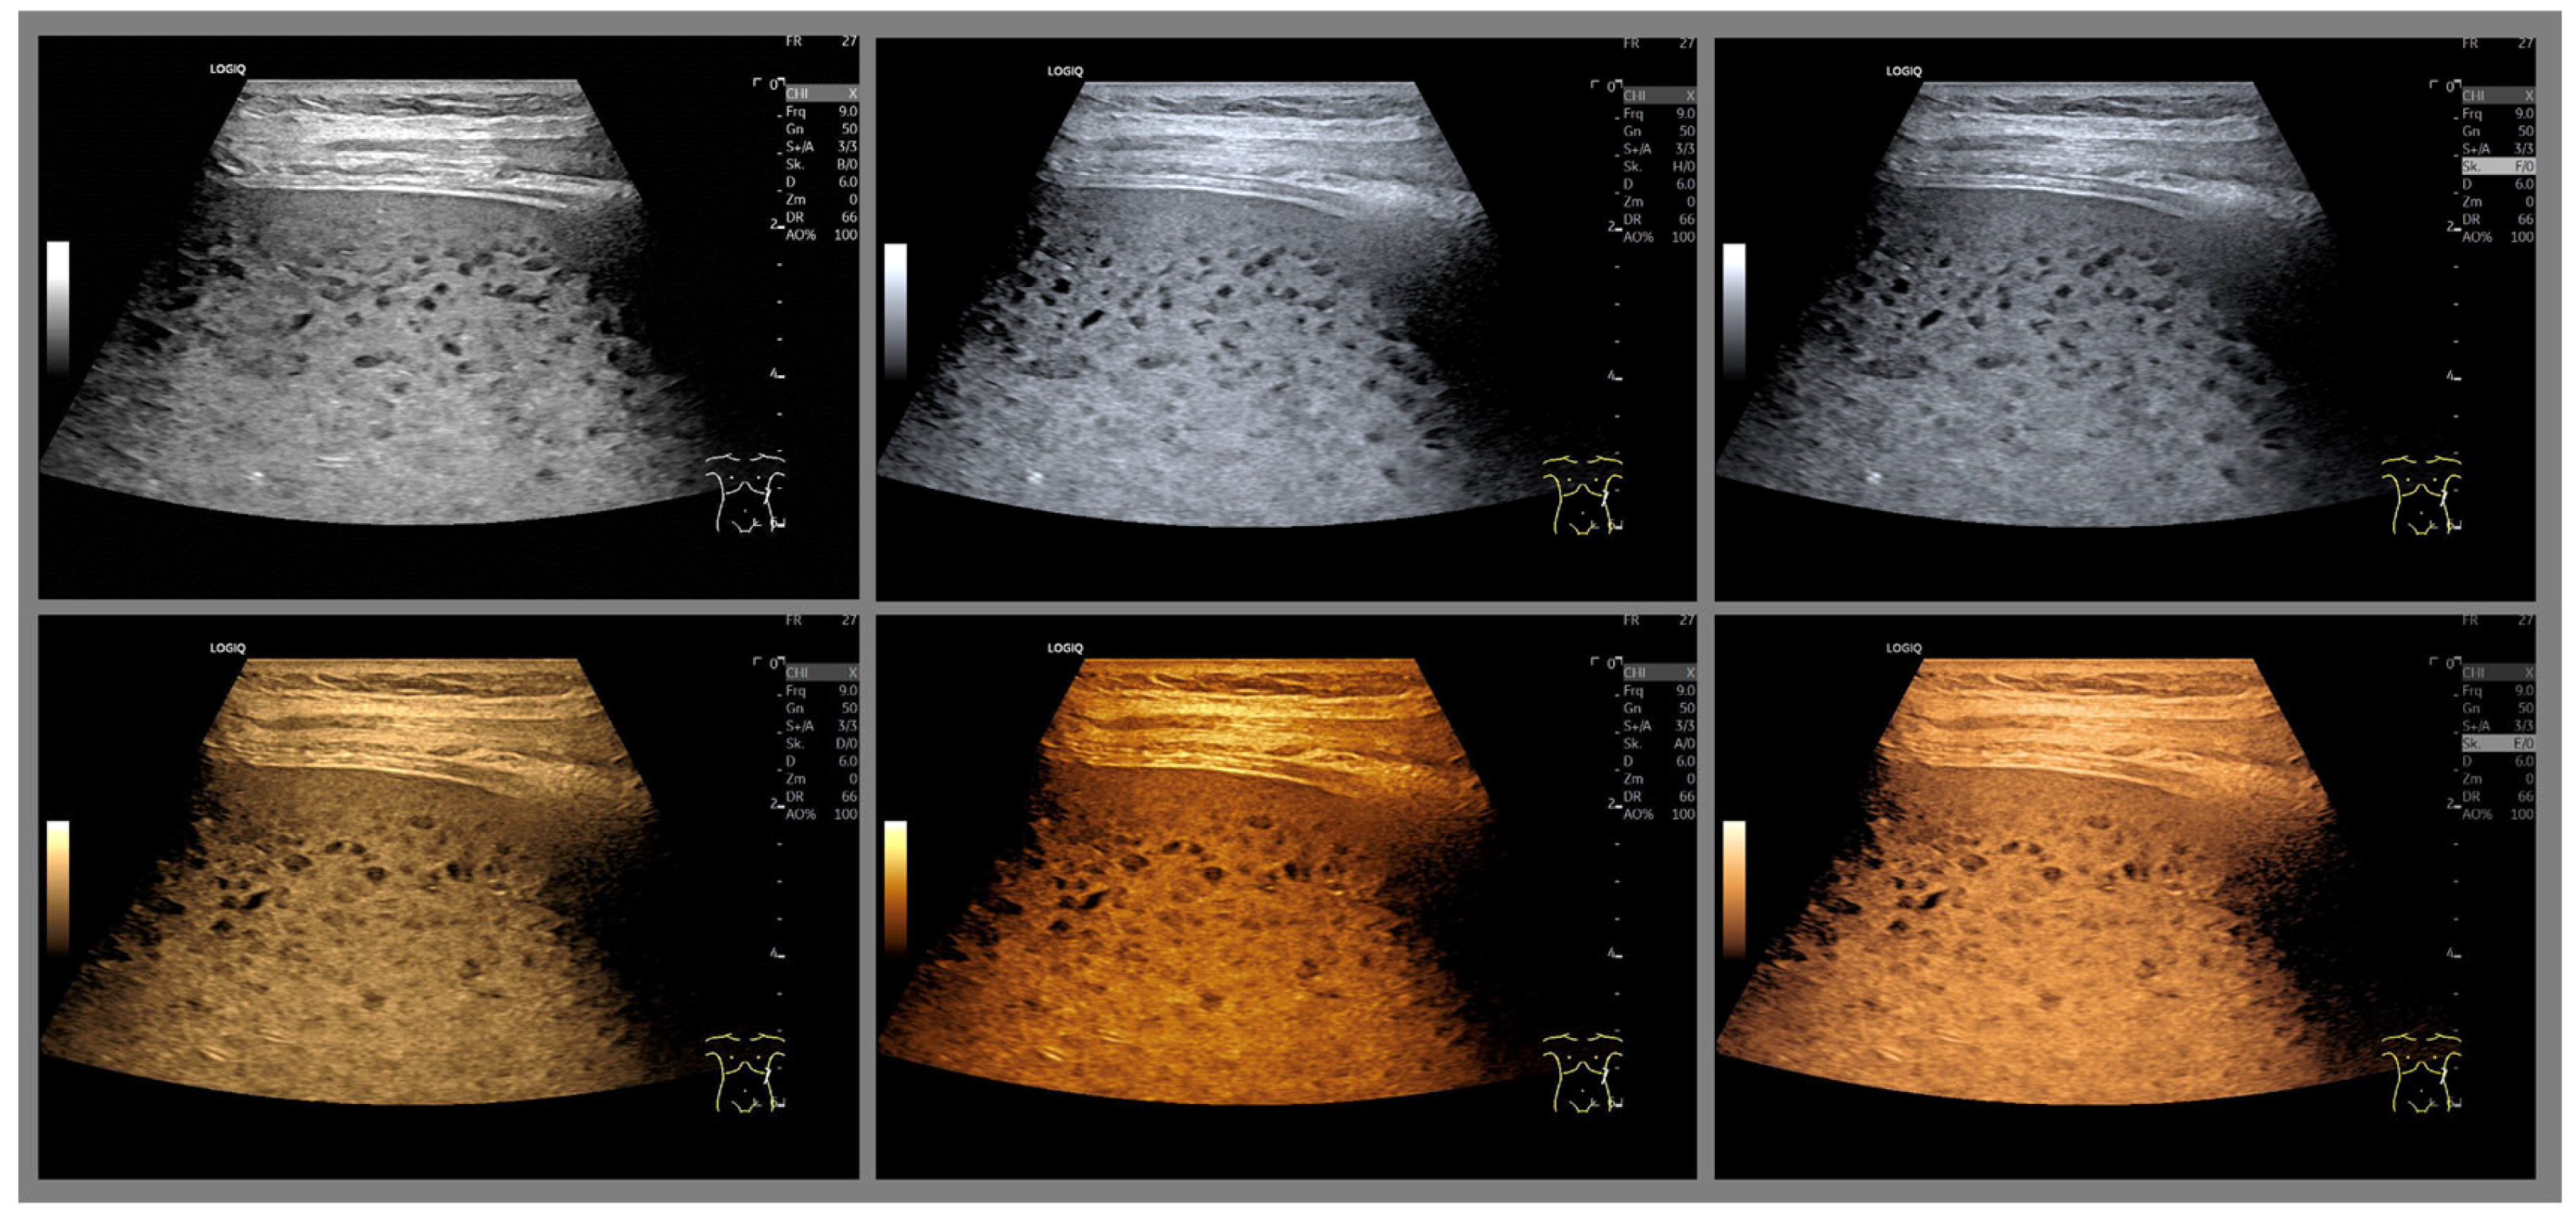

- The combination with speckle filters available in all high-end devices, similar to the low-pass filters used by Bleck et al. (1994) for tissue visualization [5], also yields significantly improved visualization results (Figure 5, Figure 6 and Figure 7). In principle, applications with new visualized texture analyses, such as random field models, are also conceivable [76,77].

Is There an Ideal Color Map?